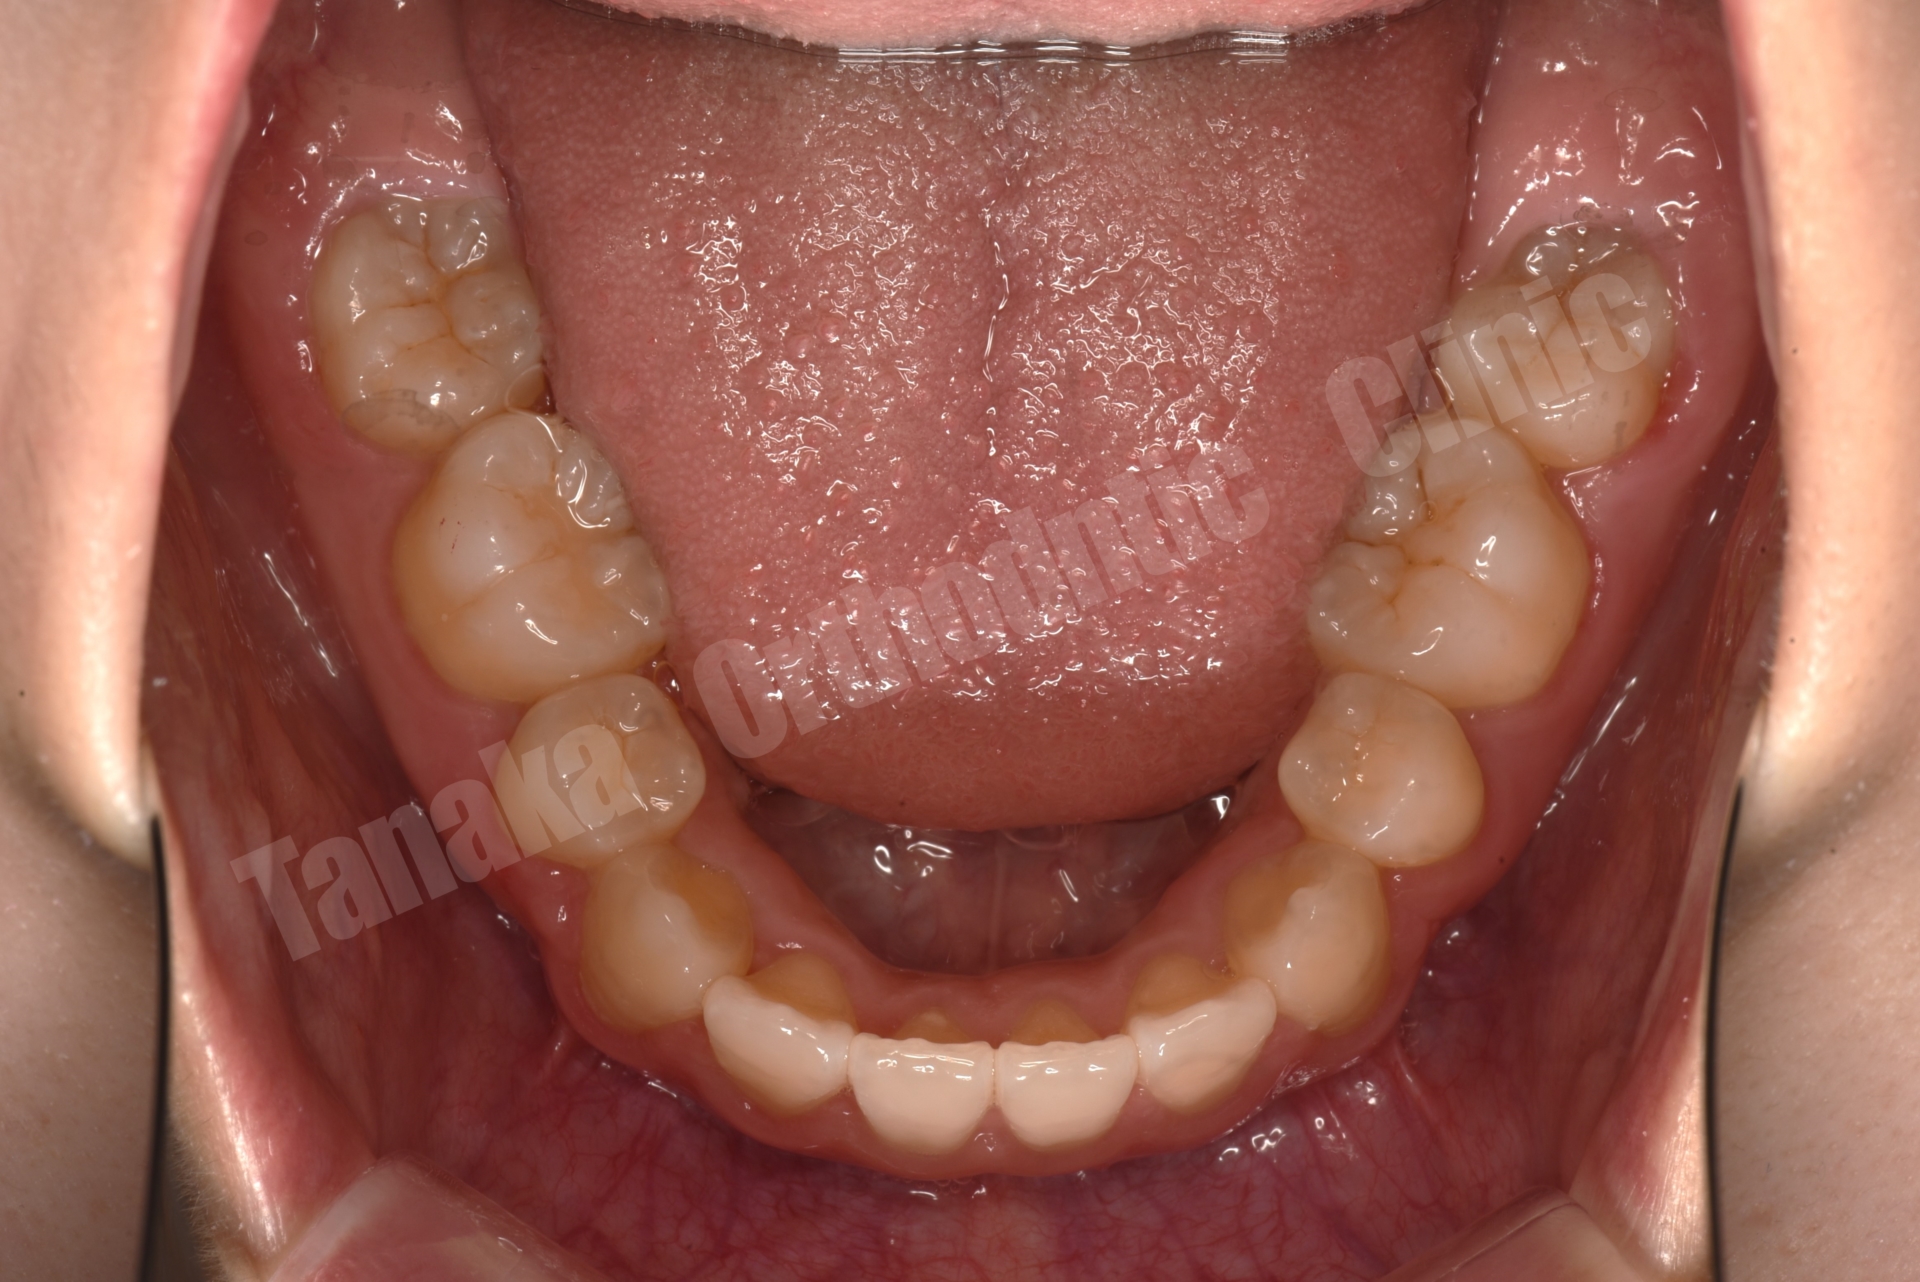

| 診断 | 上顎前突傾向(下顎骨の後方位)、上下顎歯列の叢生、上下左右8番を認める |

上下前歯部に叢生(がたがた歯列)

下顎前歯(L1)が前方に傾く「唇側傾斜」

上下4本の小臼歯を抜歯後、矯正装置を装着